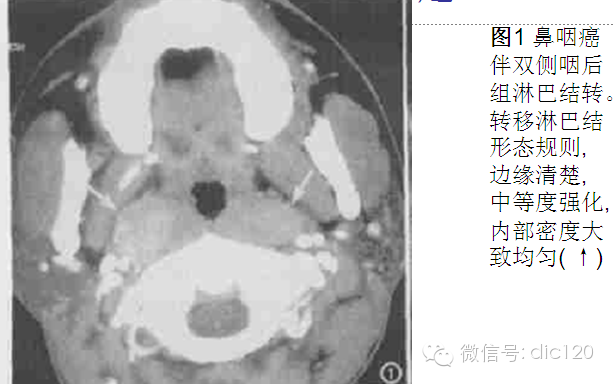

转移淋巴结发生部位和原发肿瘤的淋巴引流区域相关,口腔癌淋巴结转移主要发生于Ⅰ、Ⅱ、Ⅲ区,而口咽癌、下咽癌和喉癌主要发生Ⅱ、Ⅲ区.鼻咽癌转移淋巴结多为双侧发生,除常见于Ⅱ、Ⅲ、Ⅳ区外,咽后组、颈后三角区为鼻咽癌淋巴结转移的特征性部位,这与其他部位原发肿瘤有极显著性差异 。故咽后组淋巴结肿大时,应首先考虑鼻咽癌可能,若同时伴有颈后三角区淋巴结肿大,则诊断准确性更高,但需与淋巴瘤鉴别。

表现为形态规则且边缘清楚与形态不规则且边缘不清楚者,其原发肿瘤之间存在极显著性差异 。鼻咽癌及甲状腺癌中,形态规则且边缘清楚者分别为 88 % 和 86 % 。口咽癌,喉癌及下咽癌中形态不规则且边缘不清者分别为59 % 和68 % , 且外侵明显。这与口咽癌、下咽癌及喉癌分化差, 恶性程度高有关。